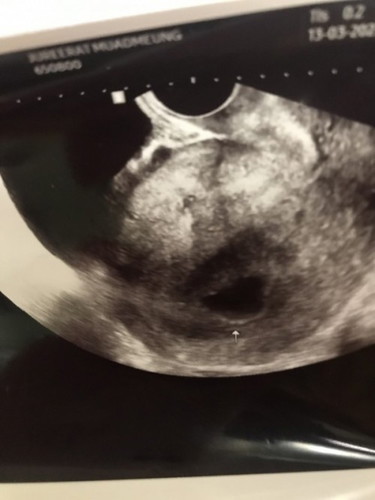

อัลตร้าซาวด์ไม่พบลูก 9สัปดาห์😢

ขออนุญาตสอบถามแม่ๆนะคะ วันก่อนไปอัลตร้าซาวด์มาค่ะ แต่ไม่พบน้อง อายุครรภ์9สัปดาห์ มีตกขาวสีน้ำตาลปนเลือดตอนปัสสาวะนิดหน่อยด้วยค่ะ หมอเลยนัดซาวด์ใหม่หลัง4สัปดาห์อีกทีค่ะ ตอนนี้แม่ยังพอมีหวังไหมคะ กังวลไปหมดแล้วค่ะ กลัวท้องลม😢